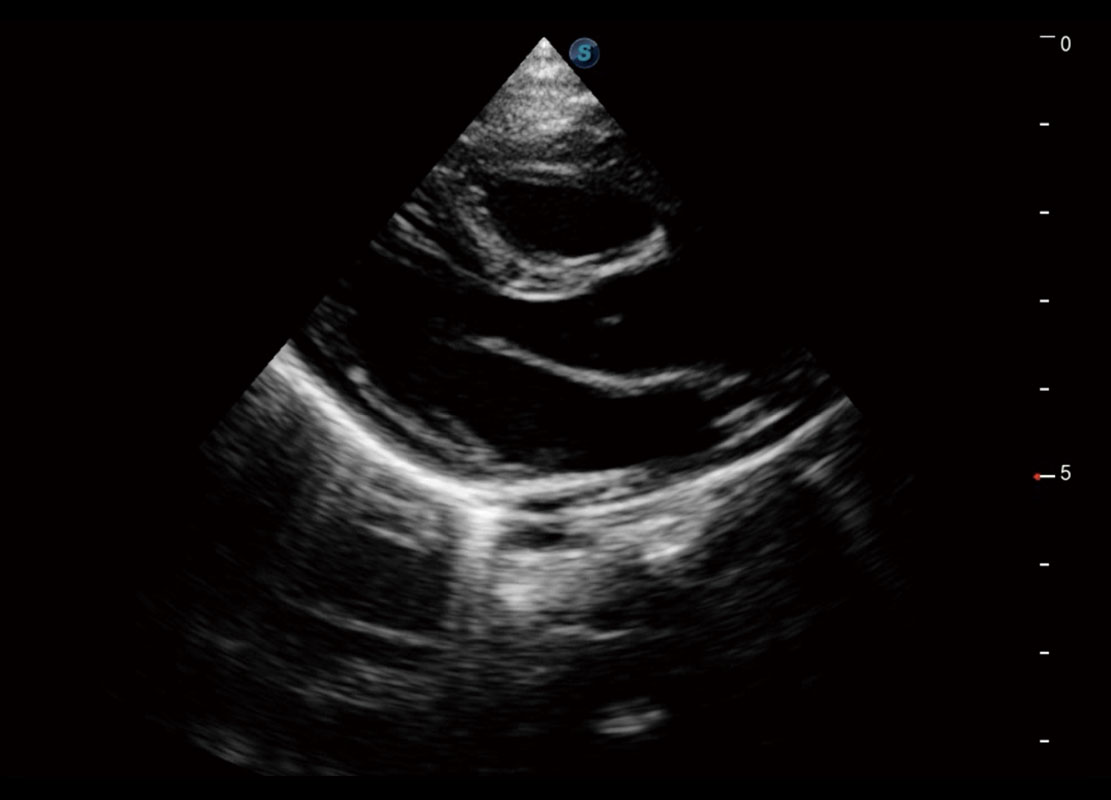

四腔切面

四腔心血流